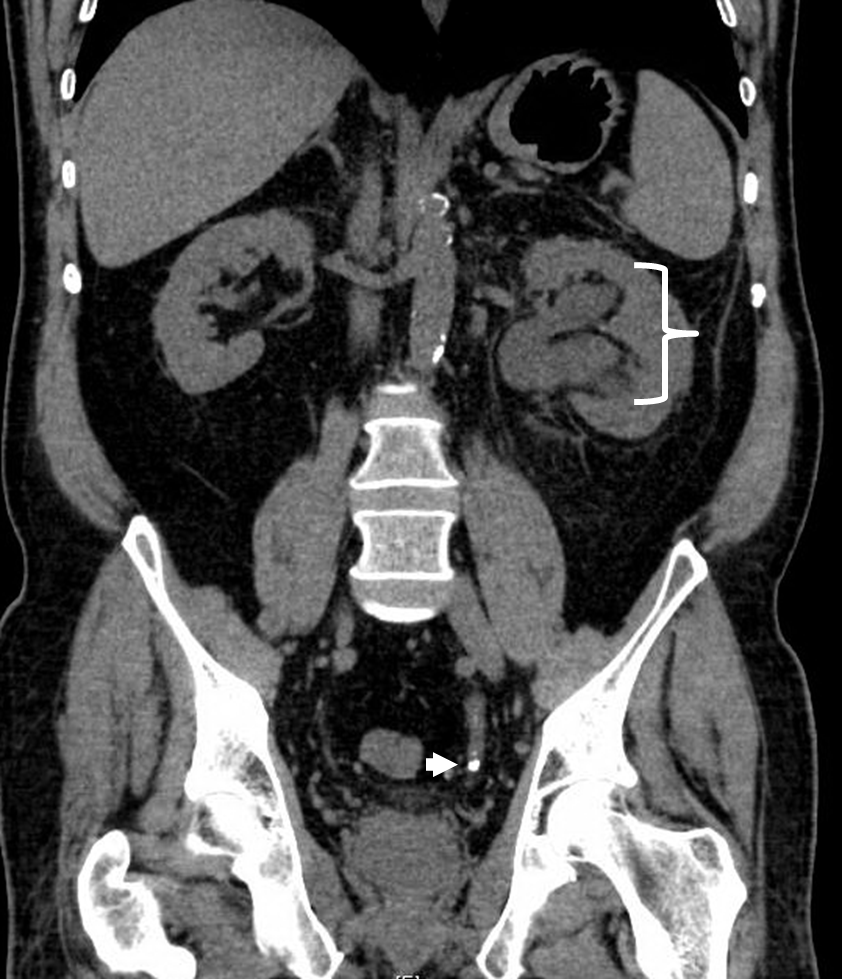

• Low-dose CT use for diagnosis of stones in pregnancy

• Increased use of ureteroscopy (URS) as primary treatment modality, ultrasonography-guided URS